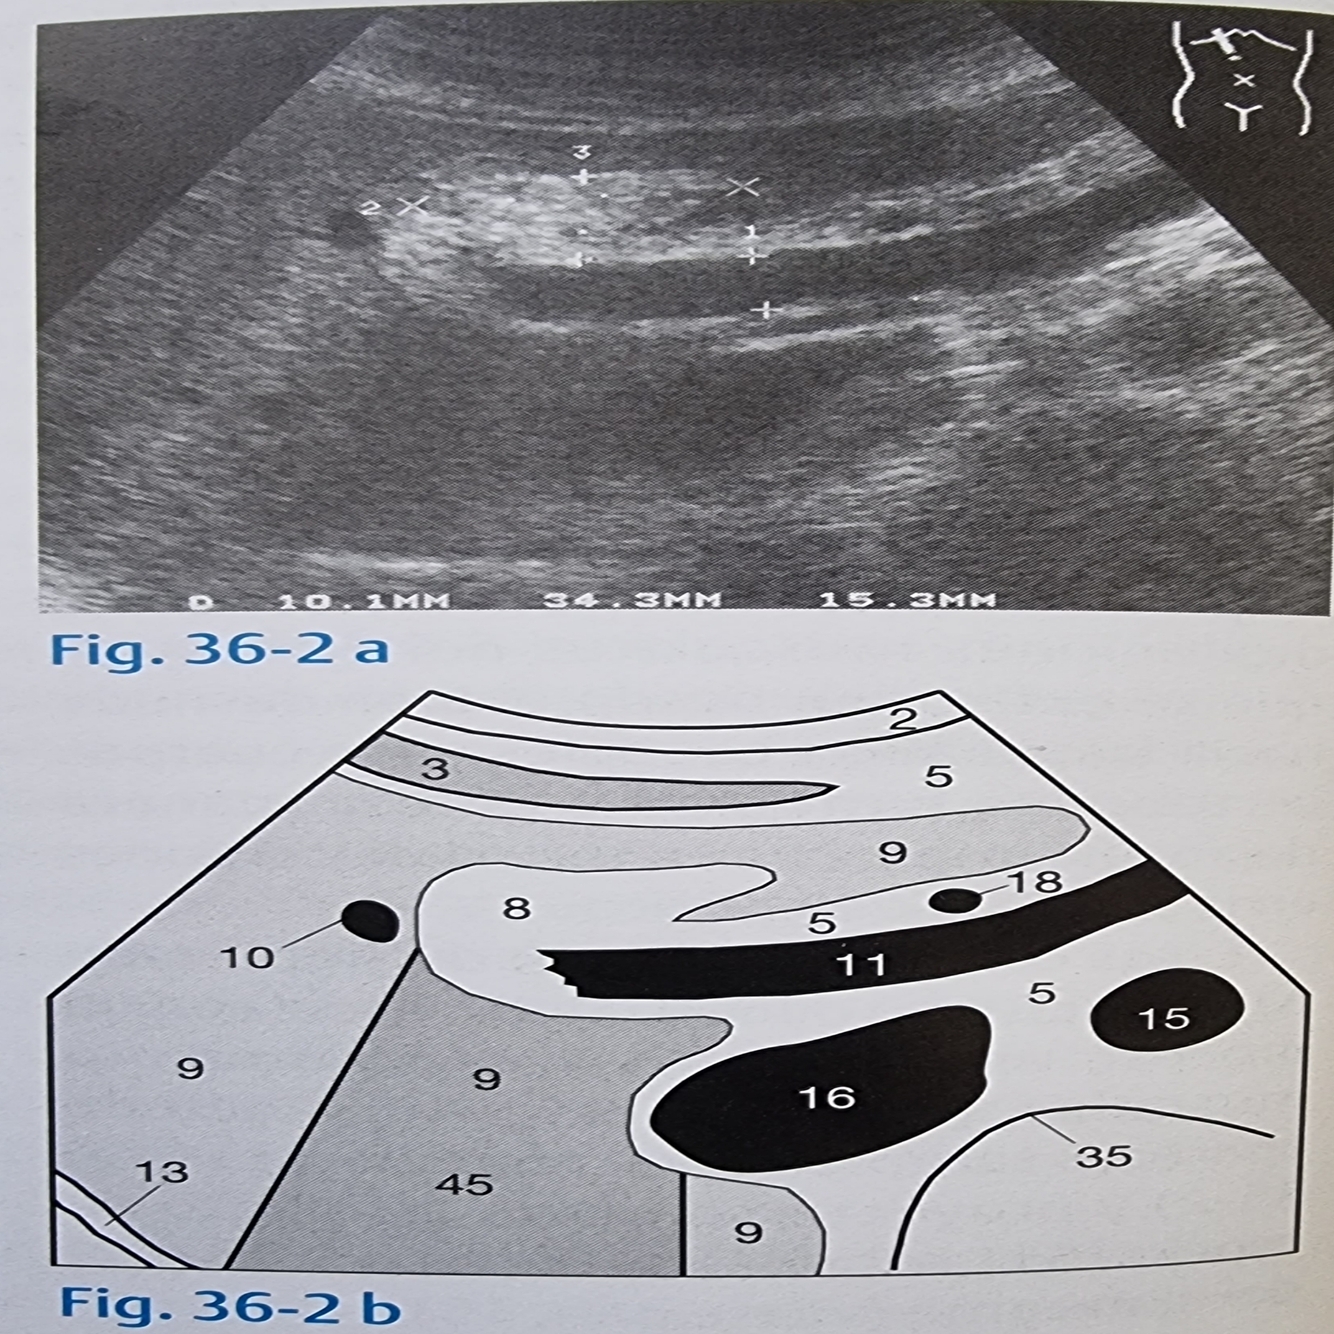

Na imagem abaixo indique as veias hepáticas e de onde elas emergem

A

10 veias hepáticas

16 veia cava inferior

O que representa os números 11, 12, 20 e 23 na imagem abaixo?

11 veia porta e suas ramificações

12 confluência da veia porta

20 veia esplênica

23 veia mesenterica superior